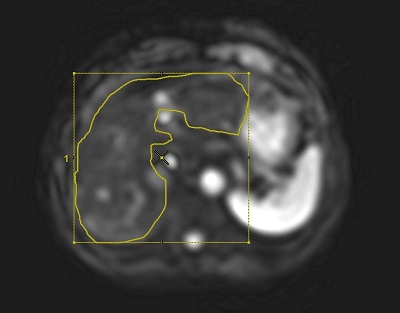

- From the measure/annotate toolbar, select the Freehand ROI icon (

). - From a mask image, draw an ROI in the non-masked area in the liver.

Figure 3. ROI drawn on mask image

- Hot spots (areas of bright signal intensity) may occur adjacent to where the active driver is placed. Do not include these areas in your ROI.

Figure 4. Example of a hot spot

- Copy/paste the ROI to an anatomic reference image and edit the ROI. For ROI edit details, see Modify measurements.

Figure 5. ROI copy/pasted to an anatomic reference image